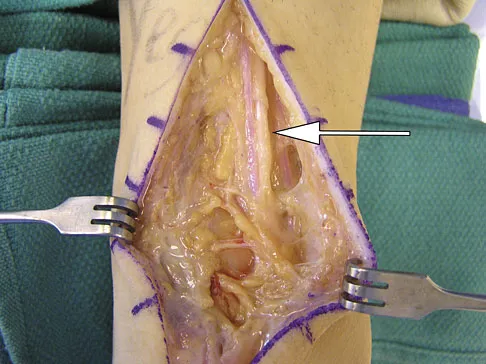

A 40-year-old man has a palpable mass over the dorsum of the ankle. He reports no history of direct trauma but notes that he sustained a laceration to the middle of his leg 6 weeks ago. Examination reveals a 4-cm x 1-cm mass. T1- and T2-weighted MRI scans are shown in Figures 12a and 12b. An intraoperative photograph and biopsy specimen are shown in Figures 12c and 12d. What is the most likely diagnosis?

Explanation